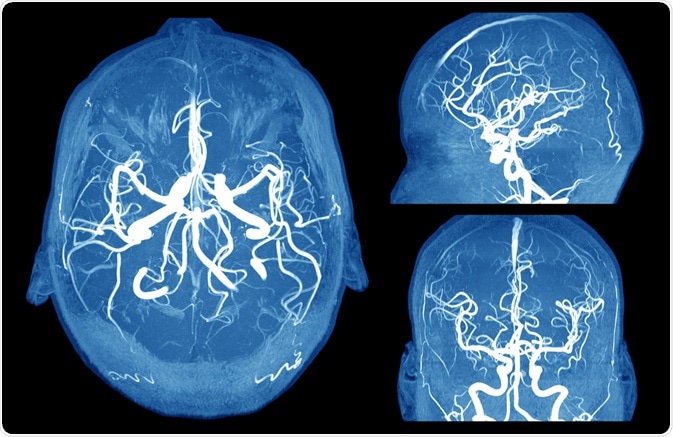

Image Credit: MriMan/Shutterstock.com